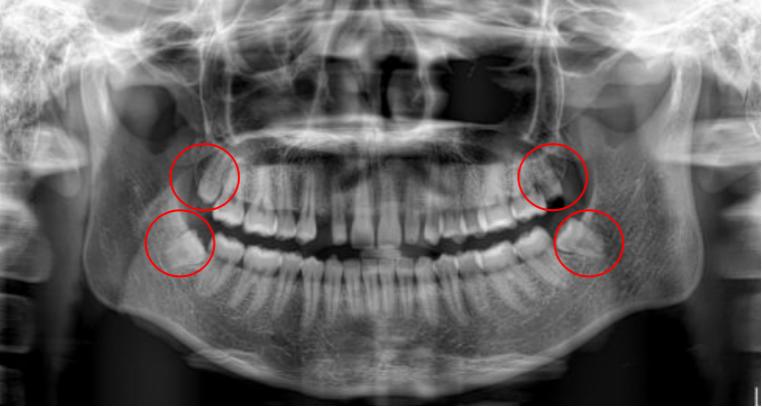

智齿也称第三磨牙,一般在18-25岁左右萌出,是人一生中最后萌出的牙齿,此时人心智基本成熟而得名。

随着人类的进化,头面部的骨骼,肌肉,牙齿也在退化,只是骨头较牙齿退化得快一些。也就是骨头变小的速度大于牙齿数目减少的速度,导致相对较小的骨头容纳不下现在的牙齿,智齿又最后萌出,没有了空间,可能完全阻生,也可能部分或完全萌出。